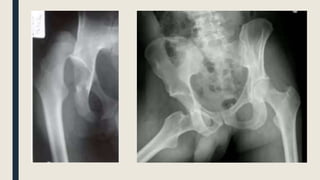

IMAGEN

■ AP Pelvis

– Línea de Shenton

– Descartar Fx

– Proyección Judet (45º)

■ Fragmentos osteocondrales / lesión acetabular

■ TAC / RMN

IMAGEN ■ AP Pelvis –Línea de Shenton – Descartar Fx – Proyección Judet (45º) ■ Fragmentos osteocondrales / lesión acetabular ■ TAC / RMN